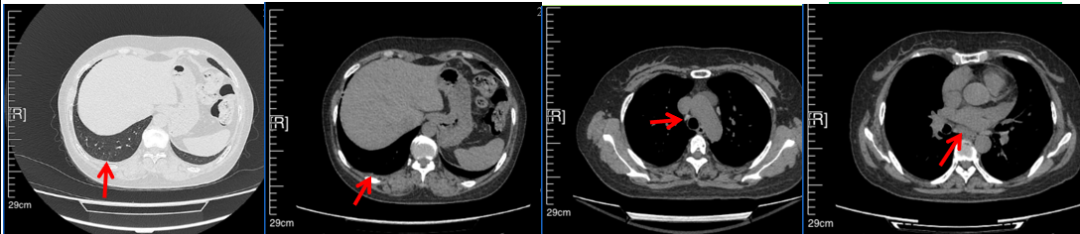

56岁,女性,无吸烟史饮酒史,既往体健。2023年02月患者体检发现肺占位性病变,胸部增强CT:右肺下叶后基底段结节;右侧锁骨上及纵隔内多发淋巴结肿大。PET-CT:右肺下叶周围型肺癌可能性大;1R、2L、3P、4R、4L及7组淋巴结转移可能性大。2023年02月就诊于本院胸外科行超声胃镜下纵隔肿物穿刺活检术,病理:结合免疫组化,符合肺腺癌。行NGS基因检测:EML4:exon20-ALK:exon20融合。PD-L1(克隆号22C3)TPS=55%。

临床诊断:右肺下叶恶性肿瘤cT1bN3M0,IIIB(第9版分期),纵隔淋巴结继发恶性肿瘤,锁骨上淋巴肿继发恶性肿瘤

治疗经过:2023年3月27日始行恩沙替尼靶向治疗至今,最佳疗效为PR,末次评效为维持PR。期间出现轻度肝功能异常(DILI 1级),对症处理后好转。截止目前PFS为26个月。

2023年2月20日基线检查

2024年6月复查PR(最佳疗效)

2024年12月复查维持PR

2025年3月复查维持PR